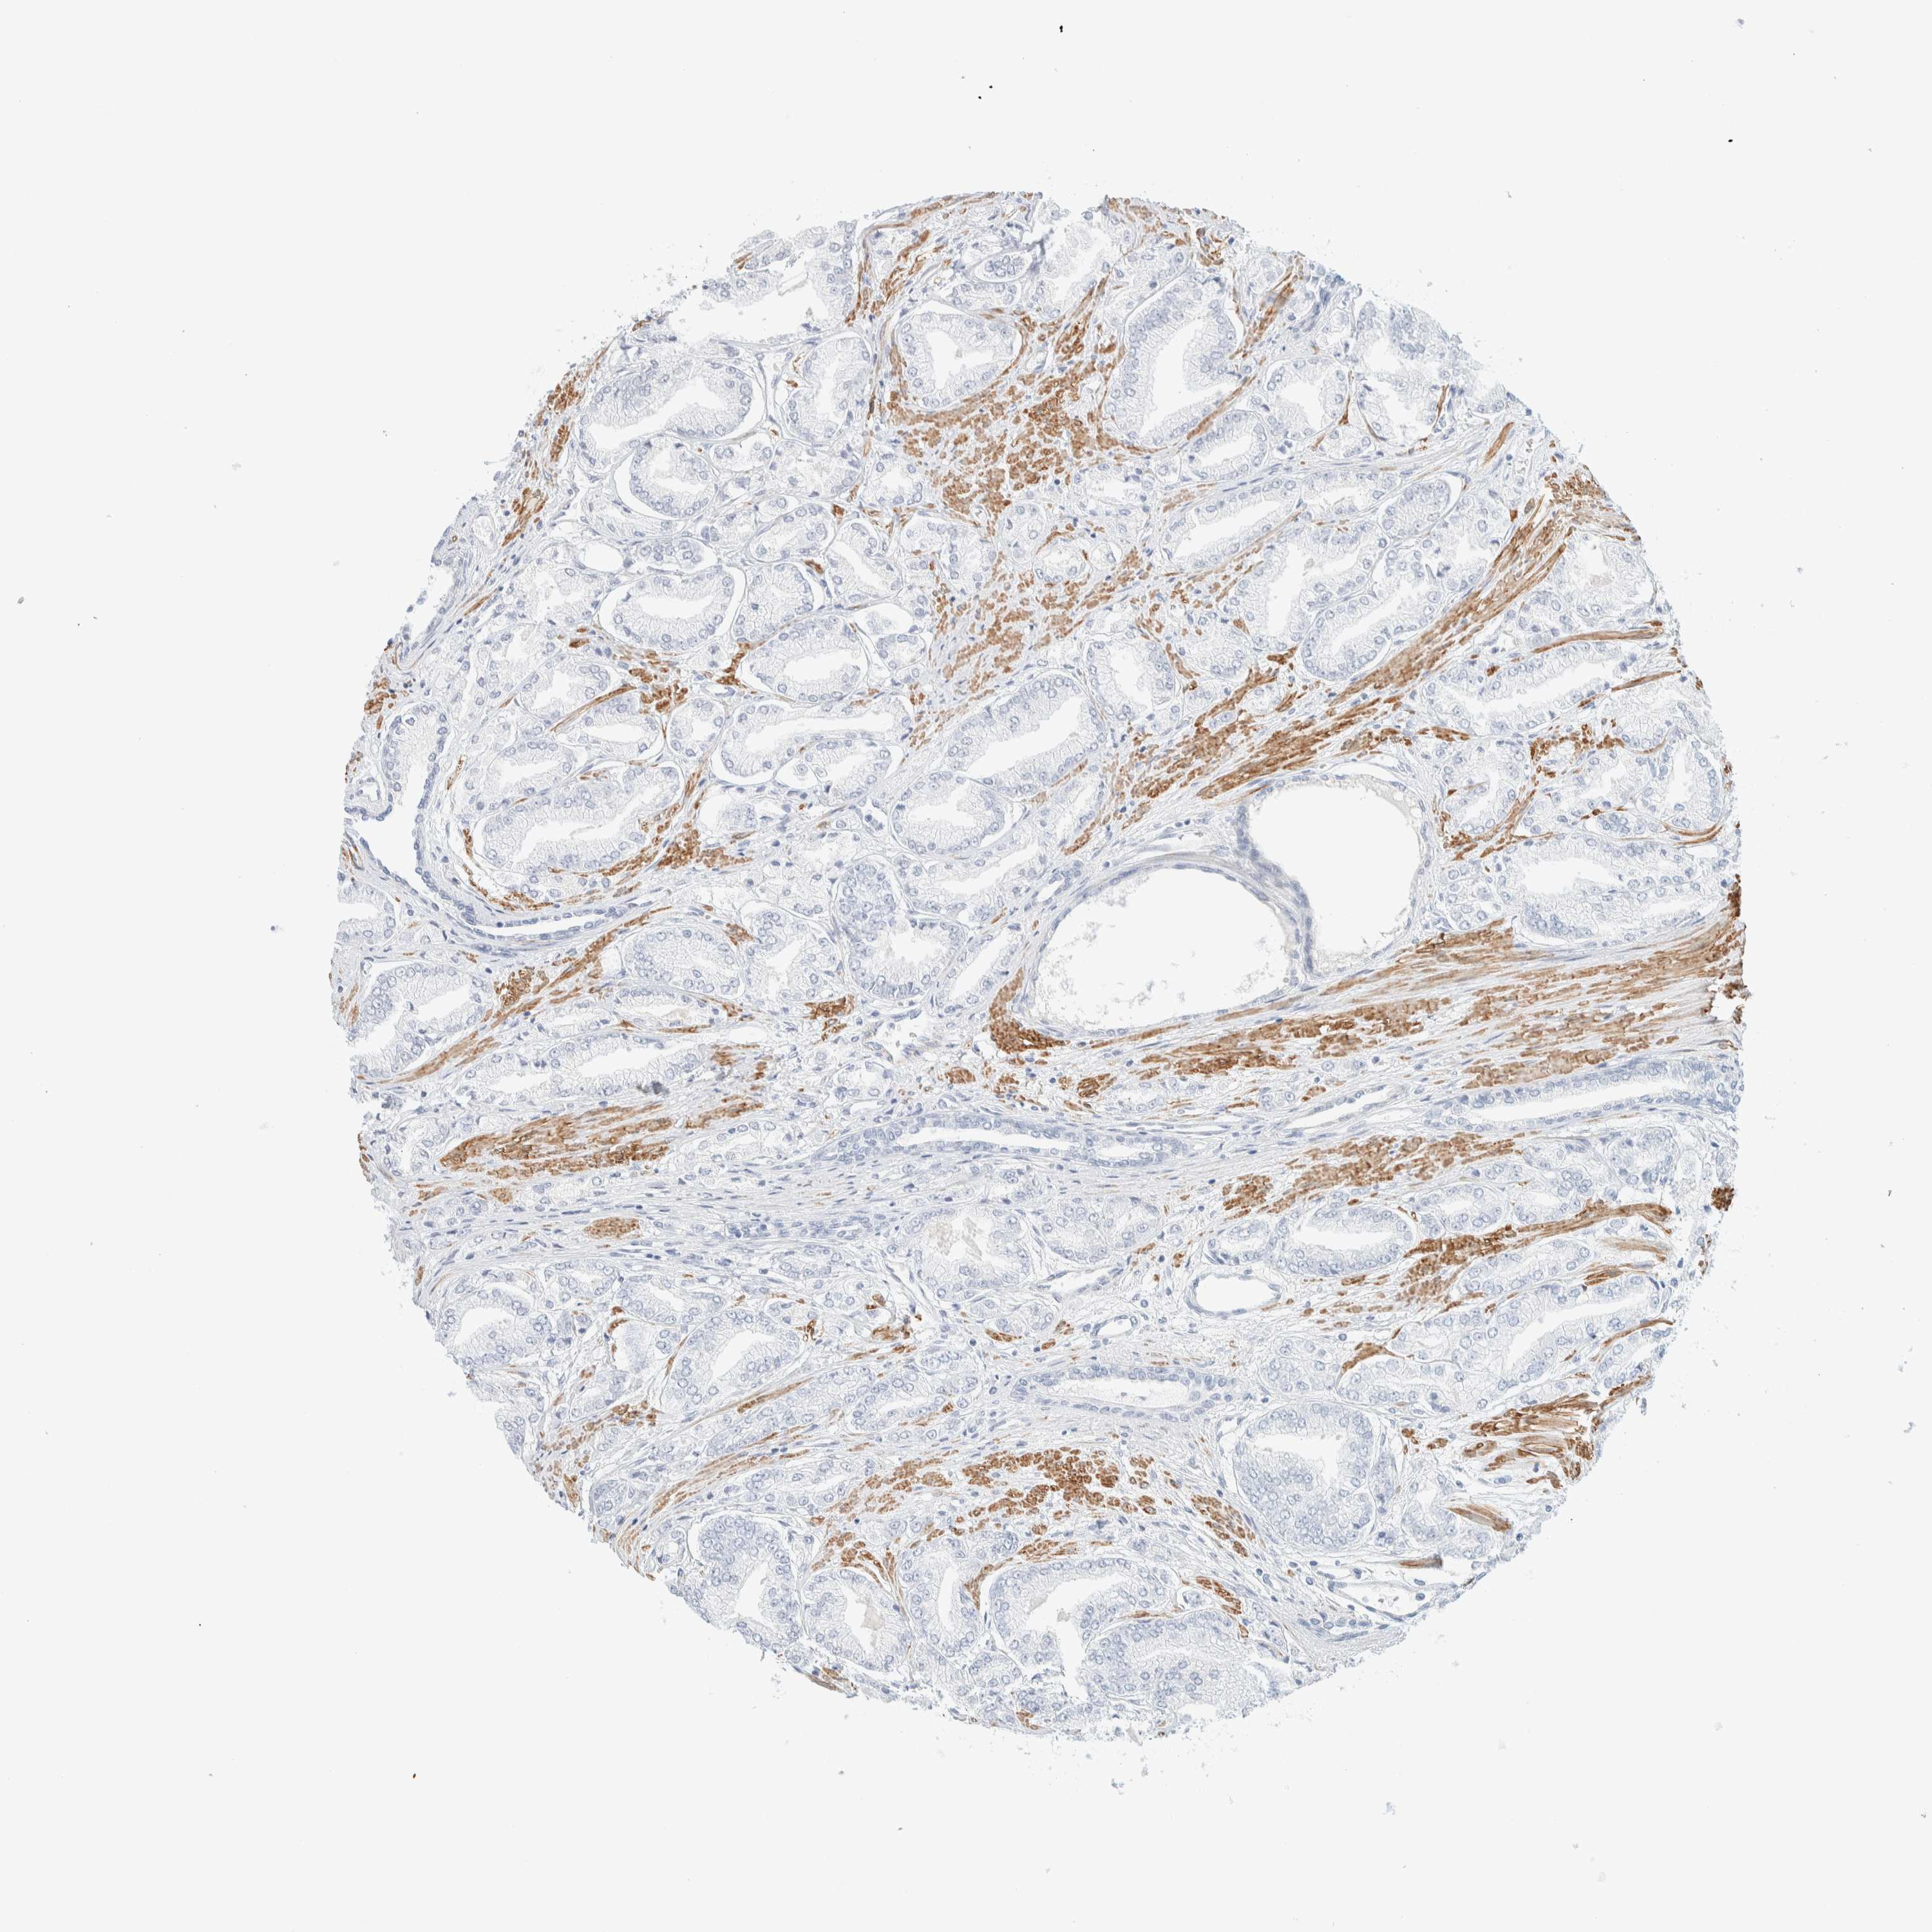

PROSTATE CANCER - Protein expressioni

A mouse-over function shows sample information and annotation data. Click on an image to view it in a full screen mode. Samples can be filtered based on level of antibody staining by selecting one or several of the following categories: high, medium, low and not detected. The assay and annotation is described here.

Note that samples used for immunohistochemistry by the Human Protein Atlas do not correspond to samples in the TCGA dataset.

Antibody stainingi

Antibody staining in the annotated cell types in the current human tissue is reported as not detected, low, medium, or high, based on conventional immunohistochemistry profiling in selected tissues. This score is based on the combination of the staining intensity and fraction of stained cells.

Each image is clickable and will lead to virtual microscopy that enables deeper exploration of all samples and also displays staining intensity scores, fraction scores and subcellular localization as well as patient and tissue information for each sample.

Antibody HPA023861

Antibody HPA026536

Staining

High

Medium

Low

Not detected

Intensity

Strong

Moderate

Weak

Negative

Quantity

>75%

75%-25%

<25%

None

Location

Nuclear

Cytoplasmic/membranous

Cytoplasmic/membranous,nuclear

Adenocarcinoma, High grade

Adenocarcinoma, Low grade